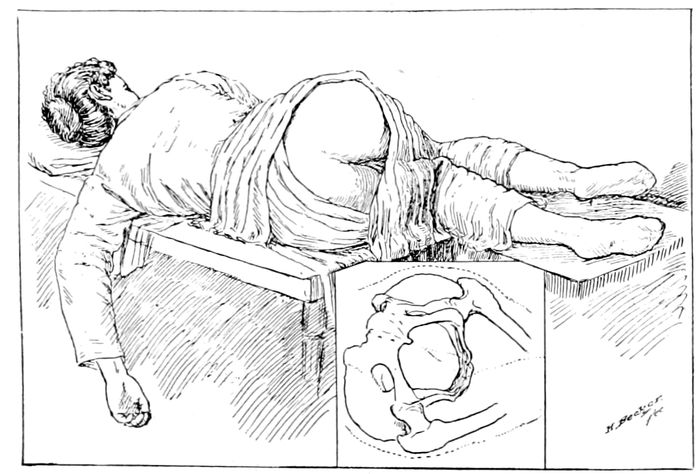

The Sims position |

241 |